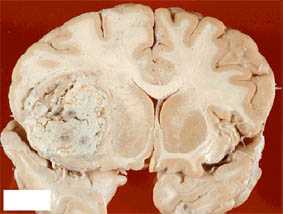

Глиобластома - наиболее злокачественная и агрессивно растущая из всех глиальных опухолей, является самой частой первичной опухолью ЦНС. Мужчины заболевают примерно в полтора раза чаще, чем женщины. Макроскопически опухоль представляет собой образование гетерогенной структуры с центральными или множественными очагами некрозаа, часто наблюдаются внутриопухолевые кровоизлияния. При гистологическом исследовании определяется резко выраженная атипия клеток с высокой митотической активностью. Четкой границы между опухолью, зоной отека и окружающей мозговой тканью нет. Симптомы повышения внутричерепного давления обычно быстро нарастают; типичны нарушения личности или появление выраженной очаговой симптоматики. Глиобластома чаще локализуется в глубинных отделах полушарий мозга с прорастанием в мозолистое тело с распространением на оба полушария в форме «бабочки». На КТ плотность опухоли весьма гетерогенна.

Центральная зона низкой плотности представляет некроз, контрастное усиление выражено в виде окаймляющего кольца с неровным внутренним контуром. В опухоли нередко отсутствует узловой компонент и она растет инфильтративно, имея многодолевое распространение. При МРТ регистрируются участки гипо-, изо- и гиперинтенсивного сигнала от стромы опухоли, некроза, кист и кровоизлияний.

Выраженный «масс-эффект» и распространенный отек белого вещества часто сопровождают даже небольшие по размерам опухоли. Во многих опухолях формируются связанные между собой отдельные узлы, в 5% встречаются мультифокальные глиобластомы. Для глиосаркомы (сочетание глиобластомы и фибросаркомы) типична поверхностная локализация, инфильтрация твердой мозговой оболочки, опухоль может давать экстракраниальные метастазы. Глиобластома имеет наихудший прогноз среди всех первичных опухолей ЦНС. Стратегия лечения - максимально полное удаление опухолевого узла с ранним подключением адъювантной внешней лучевой и химиотерапии. Несмотря на высокую злокачественность глиосарком, они достаточно четко отграничены от окружающей мозговой ткани и поэтому возможно их блоковое удаление вместе с проращенной твердой мозговой оболочкой (технология, аналогичная удалению конвекситальных менингиом) с предотвращением раннего локального рецидива. При применении агрессивной комбинированной, мультимодальной химиотерапии, включающей последовательное применение различных химиотерапевтических схем, повторных операций и лучевой терапии удается повысить среднюю выживаемость до 12-16 мес.